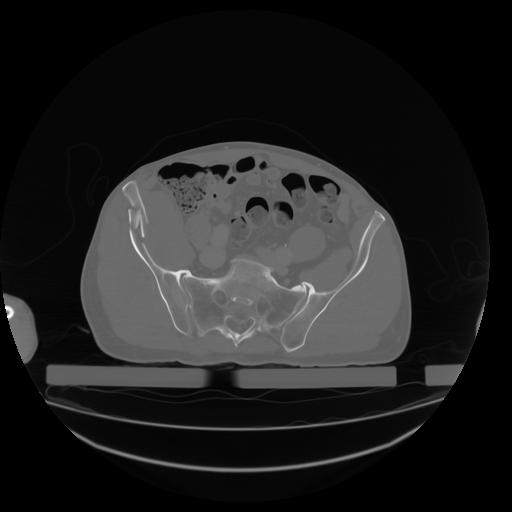

27 CUERPO,CE,Axial,3.0,CUERPO,,